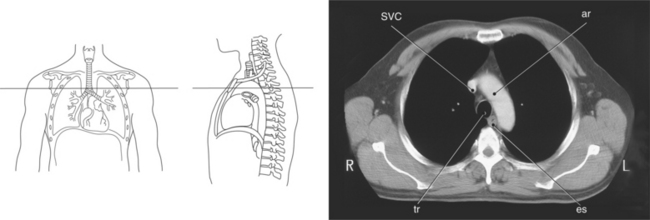

Figure 6.5 Axial CT scan of thoracic inlet.

Key: ma, Manubrium; sta, sternal angle; b, body; tho, thoracic outlet; SCjt, sternoclavicular joint; cl, clavicle; tha, thoracic aperture; T1, first thoracic vertebra; rib, first rib.

The three main branches of the aortic arch are the brachiocephalic trunk, left common carotid artery, and left subclavian artery (Figure 6.84). The brachiocephalic (innominate) trunk is the first major vessel and the largest branch arising from the aortic arch. It ascends obliquely to the upper border of the right sternoclavicular joint, where it divides into the right common carotid and right subclavian arteries (Figures 6.85 and 6.86). The right common carotid artery ascends the neck lateral to the trachea to the level of C4, where it divides into the right external and internal carotid arteries. The right subclavian artery curves posterior to the clavicle into the axillary region, where it becomes the right axillary artery. The left common carotid artery is the second vessel to branch from the aortic arch. It arises just behind the left sternoclavicular joint and ascends into the neck along the left side of the trachea to the level of C4, where it bifurcates into the left external and internal carotid arteries. The left subclavian artery arises from the aortic arch posterior to the left common carotid artery and arches laterally toward the axilla in a manner similar to that of the right subclavian artery, where it continues as the left axillary artery (Figures 6.85 through 6.88). The right and left internal thoracic arteries arise from the respective subclavian artery at the base of the neck. They run deep to the ribs, just lateral to the sternum, to supply blood to the anterior portion of the thorax (Figure 6.89). The common carotid arteries supply blood to the head and neck, whereas the subclavian arteries supply blood to the upper extremities.

The superior vena cava receives blood from the head and neck via the internal and external jugular veins and from the upper extremities via the subclavian veins (Figures 6.84 and 6.90). The subclavian veins arise from the axillary veins and course posterior to the clavicles. They receive blood from the external jugular veins before uniting with the internal jugular veins behind the sternoclavicular joints, where they continue as the brachiocephalic veins. The left brachiocephalic vein courses across the midline, anterior to the branches of the aorta, to unite with the right brachiocephalic vein just posterior to the costal cartilage of the right first rib. The union of the two brachiocephalic veins forms the superior vena cava, which empties into the right atrium of the heart (Figures 6.75 and 6.76).